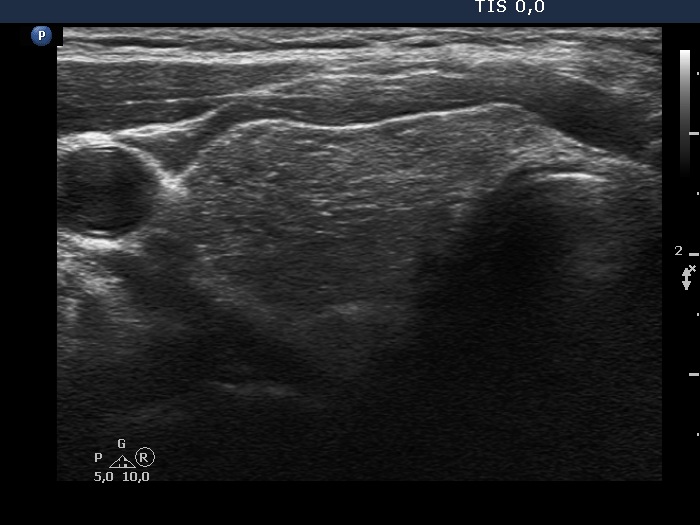

First examination (first row of images):

Clinical presentation: A 37-year-old man was referred for an evaluation of a 'lump in the throat' feeling.

Functional state: subclinical hypothyroidism with TSH 5.01 mIU/L, FT4 13.6 pM/L.

Palpation: the left lobe was suspicious containing a small nodule.

Ultrasonography. The thyroid was moderately hypoechogenic and displayed fibrosis. There was a relatively larger hypoechogenic lesion in the central part, and other smaller ones in the dorsal part of the left lobe. The dimensions of the largest lesion were 11x10x13 mm (width, depth, and length, respectively), the volume was 0.75 mL. The vascularization was not specific.

Aspiration cytology resulted in Hashimoto's thyroiditis. Atypia of unknown significance; the possibility of a Hürthle-cell tumor cannot be excluded.

We told the patient that the risk of malignancy is around 5%. We offered a follow-up examination instead of a surgery and suggested a repeat FNA in six months.